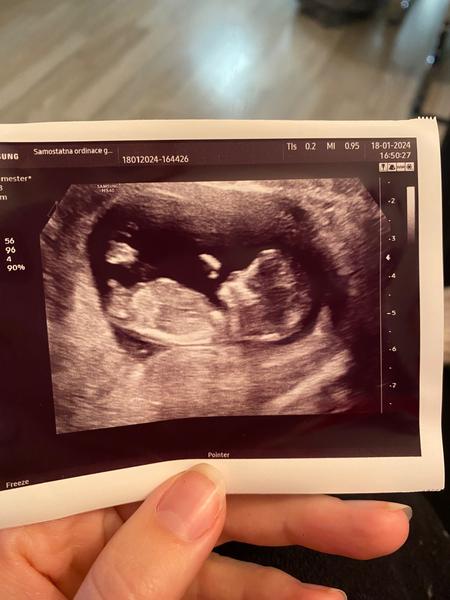

Ahoj holky a jak to vidíte tady,prosím? 🙂

@daniela1995 hele asi vidím to co ty, jen si to bojíš říct nahlas. Já vidím holčičku🙂

@daniela1995 taky se mi zdá,že je to holčička 🥰

@daniela1995 holka!

@neria55 myslíš ? Moc se bojím důležité je aby to bylo hlavně zdravé , ale holčičku bych si moc přála 🥹🥰❤️